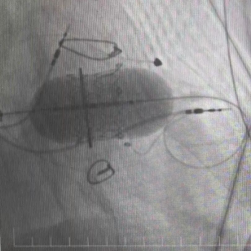

三尖瓣置換術

永久起搏器植入術“這相當于用微創的方式,完成過去需要三次手術才能解決的問題。”陳文生主任解釋說,介入操作無需再次開胸,只需通過血管穿刺送入導管,對患者創傷小,尤其適合這種多次手術后的高危患者。

手術臺上,心臟大血管外科陳文生團隊通過細致的影像引導,將球囊送至原有瓣膜處進行擴張,隨后將新的生物瓣精準釋放在預定位置 。最后,在心臟穩定的狀態下,順利植入了永久起搏器。整個過程中,患者生命體征平穩。